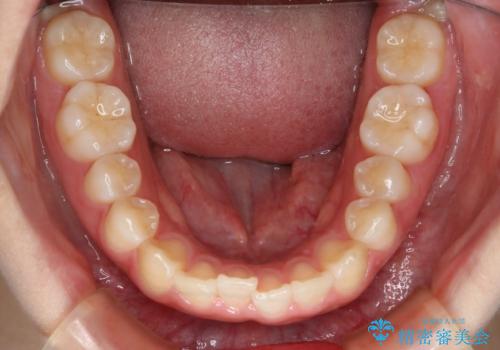

- 前歯のガタつきの改善を主訴に来院された患者様です。

ガタつきによる上顎正中の空隙や歯の突出感も気にされていました。

費用を抑えたいとの事だったので歯の移動量なども考慮し、インビザライン・ライトパッケージでの治療を計画しました。